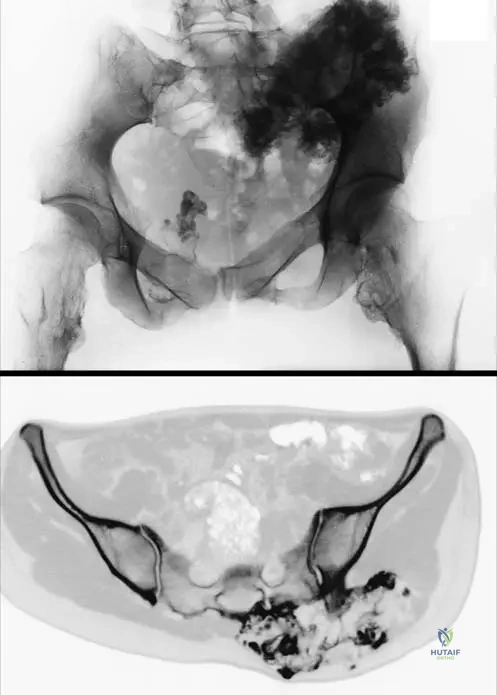

Question 62

A 19-year-old female with hereditary multiple exostoses presents with a painful mass in her left groin region. A CT scan reveals an osteochondroma arising from the iliac bone. What is a potential complication of osteochondromas in the pelvic region?

View Answer & Explanation

Correct Answer: A

Rationale: Osteochondromas in the pelvic region, particularly those arising from the iliac bone (as shown in Fig. 1.55), can grow large and impinge on adjacent neurovascular structures. Sciatic nerve compression is a known complication, leading to pain, numbness, or weakness in the lower extremity. While bladder dysfunction could theoretically occur with very large pelvic masses, nerve compression is a more direct and common complication. The other options are less directly related to an iliac osteochondroma.

A 16-year-old male with hereditary multiple exostoses is being evaluated for a large, firm mass on his distal femur. He reports no pain, but the mass has been slowly growing. Radiographs show a broad-based osteochondroma. What is the typical location of osteochondromas in patients with HME?

Correct Answer: C

Rationale: The text explicitly states that osteochondromas in HME are "mainly at the metaphyses of long bones at the extremities." This is their characteristic location, as they arise from aberrant growth plate cartilage. They are rarely found in the diaphysis, epiphysis, articular cartilage, or bone marrow. Fig. 1.51 also shows large tibial, fibular, and femoral osteochondromas consistent with metaphyseal involvement.